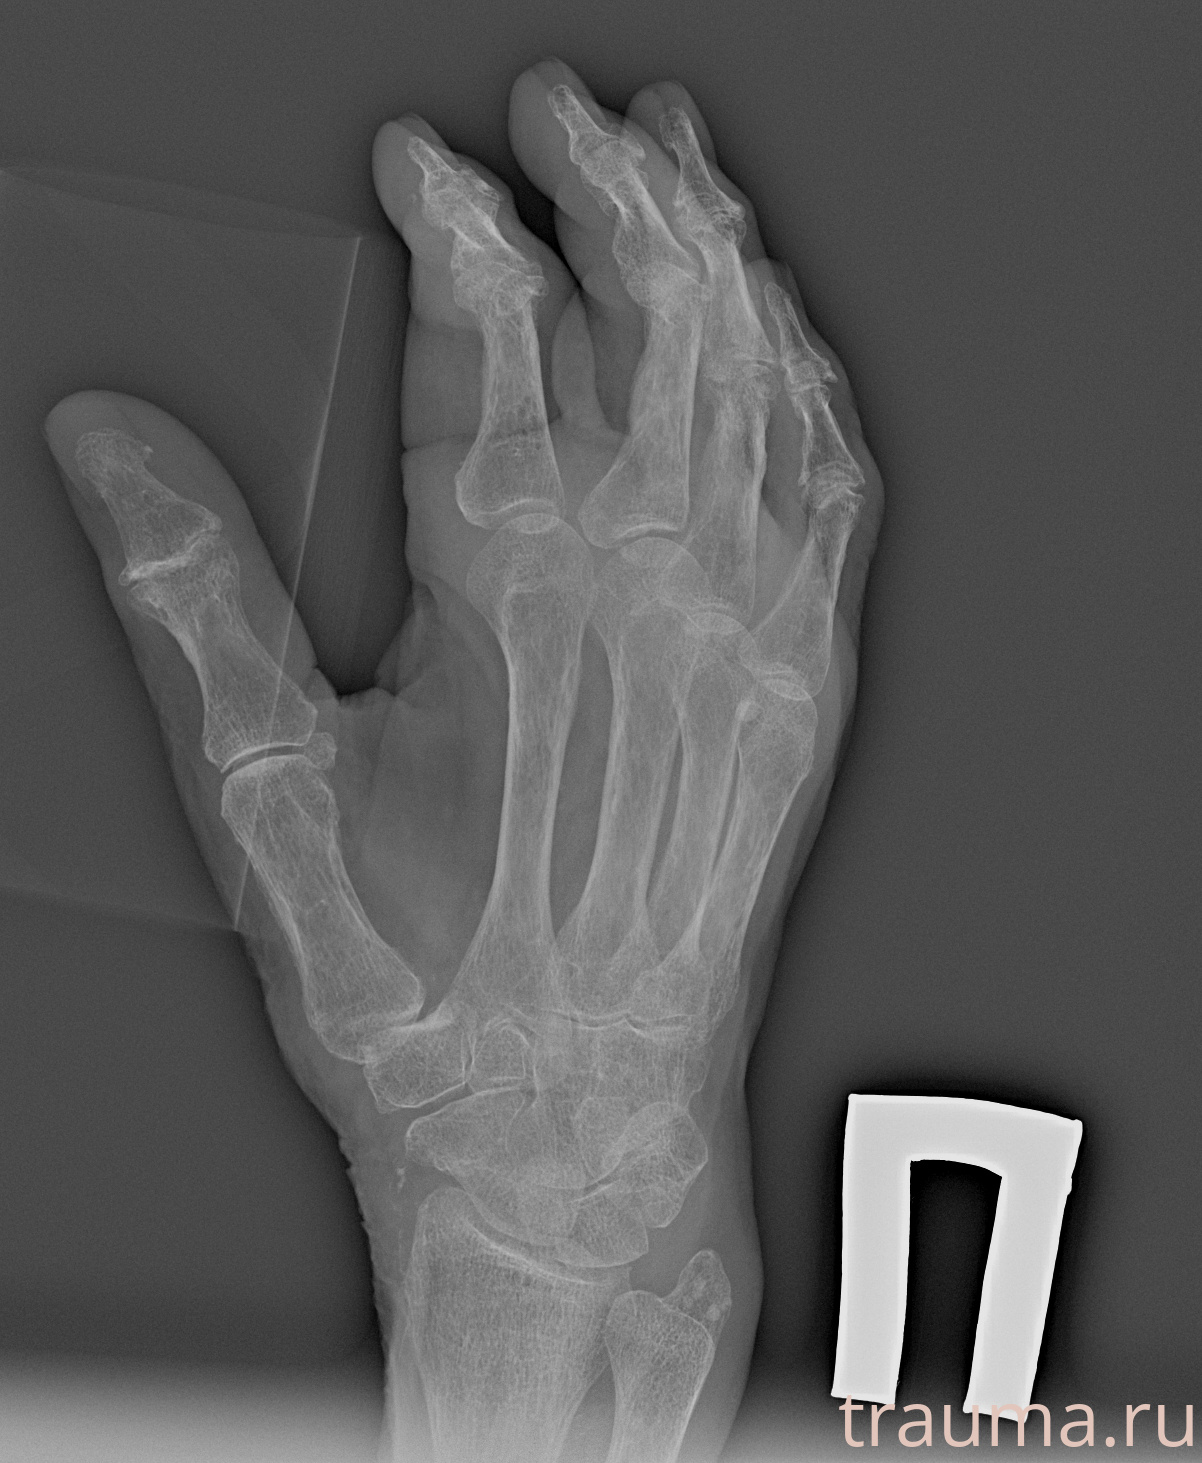

Рентгенограммы

Рентген на дому: по вашему адресу приезжает врач-рентгенолог, травматолог-ортопед с мобильным рентгеновским аппаратом, проводит диагностику травмы или заболевания, делает необходимые рентгенограммы, дает рекомендации по дальнейшему лечению. Получить качественные снимки в домашних условиях возможно благодаря уникальной методике, разработанной МосРентген Центром для института  Склифосовского